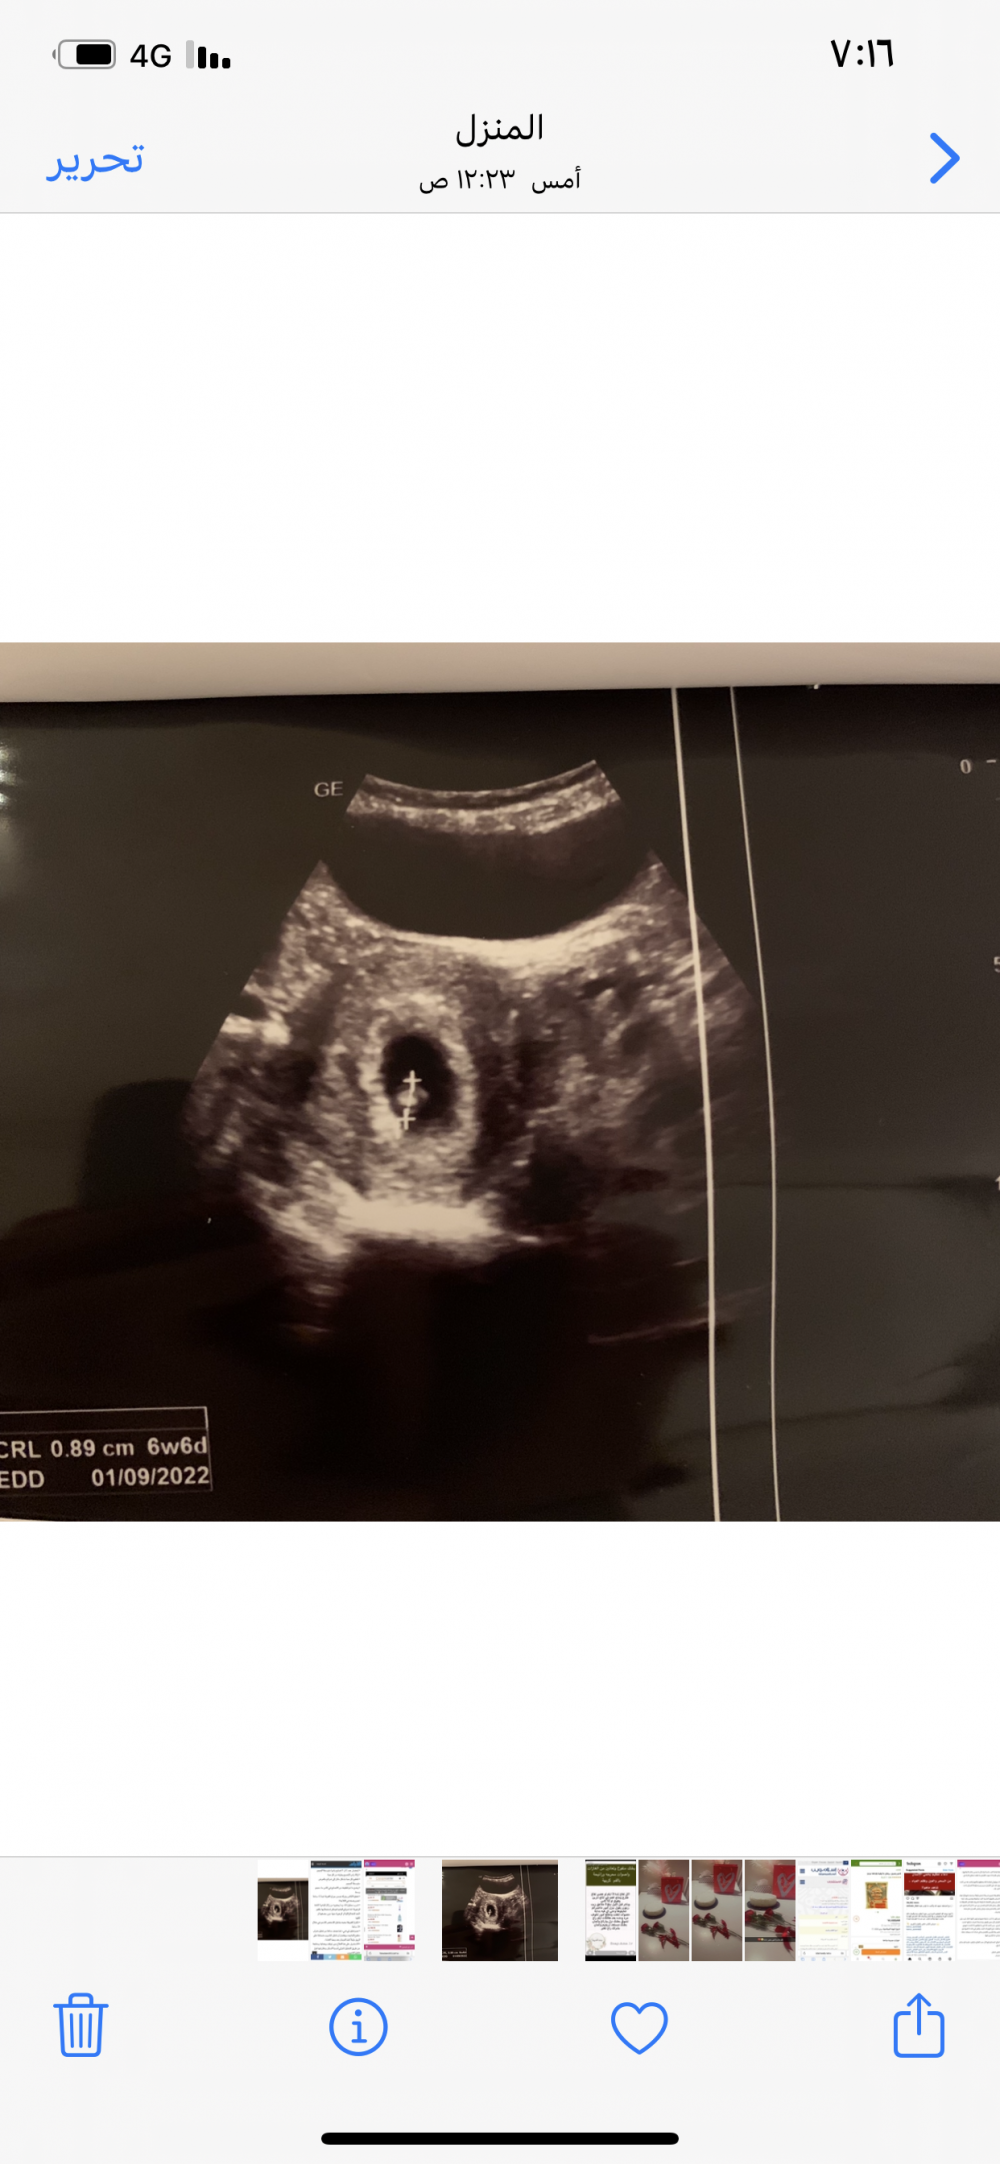

اليوم رحت وقهرتني عيت تقولي شي عن الجنس قلت لها قالولي ولد قالت اوكي اذا قالو لك ليش تسالين قلت بتاكد قالت مو واضح طبعا حكومي دكتورتي مسافره ورحت لغيره 😕 وهذي صورته معطيني ظهره 🥲😍

سارونه شوفي لي في ٧ اسابيع